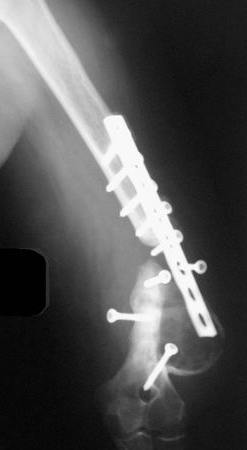

Второй случай, также после множественных операций:

пластина, аппарат, серкляж и парез нерва.

Также ревизия, из-за низкого состояния доступ был

сделан через остеотомию локтевого отростка.

Ложный сустав фиксирован двумя локинг плейт с

аутокостной пластикой, также через два месяца увидели признаки консолидации.

Движение в суставе разрешили в две недели.